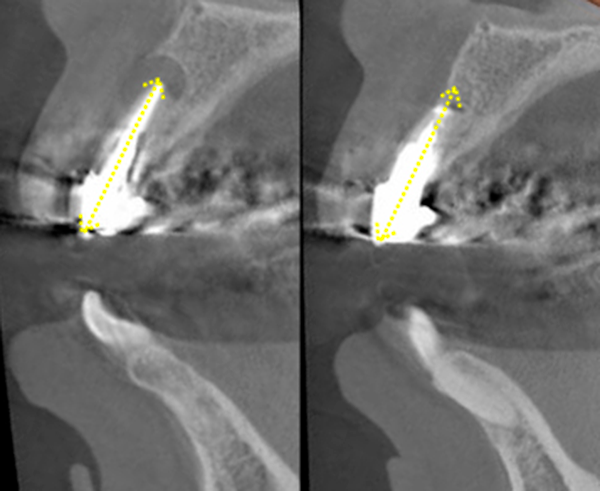

This is a surgical procedure that includes extraction. One such procedure is called " apicoectomy." (Figures 20 and 21)

The brief description of this procedure is that the contaminated root apex is cut away.

First, the gum around the root apex is detached to expose the root apex. Then,after removing about 2 mm of the tip, the bacteria around the tip are scraped off with scraper.

...the roots become shorter and less supportive of the teeth.

In other words, as the roots that support the tooth become shorter, the tooth is more likely to shake, and if it becomes infected with periodontal disease, even slightly, it will have to be extracted.